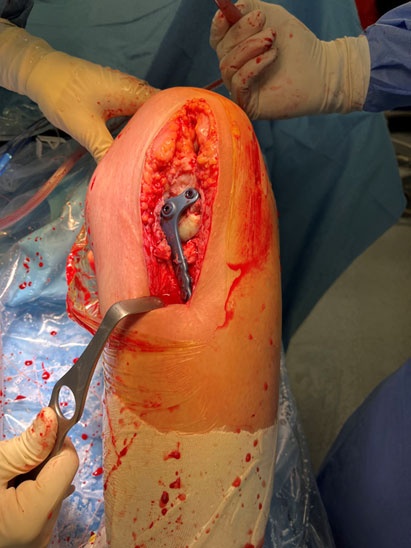

Tibial tunel drilling thanks to a custom made guide arthroscopically assisted

Tibial tunel drilling thanks to a custom-made guide arthroscopically assisted

Final aspect after bone grafting and fixation of the posterior tibial tendon allograft